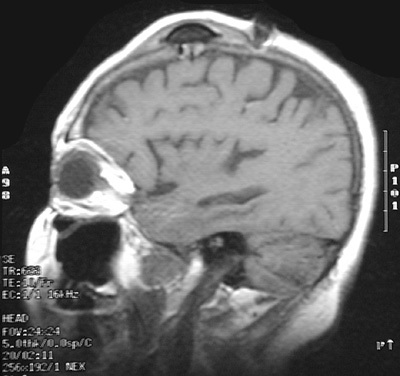

| In the coronal view above and the sagittal view below with these T1 weighted MRI scans can be seen an Ommaya reservoir placed under the scalp with catheter extending into the ventricle in a patient with a carcinoma metastatic to the meninges. Such a reservoir provides a means for delivering chemotherapeutic agents in high concentration. |